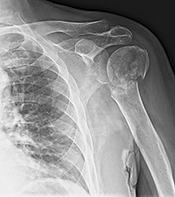

Fracture of upper humerus: Commonest shoulder fracture is that of upper end of the arm (humerus). Upper end, which is like a ball, articulates with the cup on the shoulder girdle bone (the scapula). Treatment of the fractures of the upper end of humerus depends upon a lot of factors.

We have an expertise in re-doing old operated fractures, and those which have not been treated properly, in the first place. The following are some of the examples: